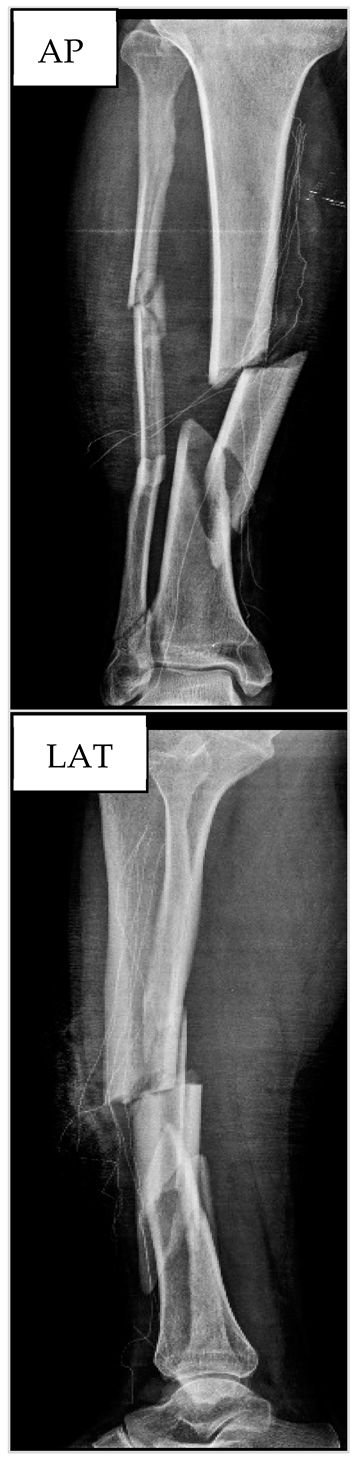

3.2. Patient nº2